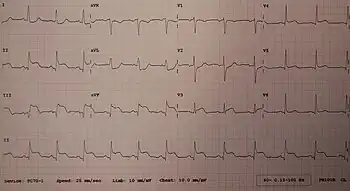

Electrocardiogram

Electrocardiograms (ECGs) are an important part in the workup of an AMI,[25] and ECGs are often repeated over minutes to hours, or in response to changes in symptoms.[25]

A rise in the ST segment, changes in the shape or flipping of T waves, new Q waves, or a new left bundle branch block can be used to diagnose an AMI.[25] In addition, ST elevation can be used to diagnose an ST segment myocardial infarction (STEMI). A rise must be new in V2 and V3 ≥2 mm (0,2 mV) for males or ≥1.5 mm (0.15 mV) for females or ≥1 mm (0.1 mV) in two other adjacent chest or limb leads.[20][25] ST elevation is associated with occlusion of a blood vessel, and may be preceded by changes indicating ischemia, such as ST depression or inversion of the T waves.[81]

STEMI equivalents include De Winter syndrome, ST depression in V1 to V4 representing a posterior MI, Wellens syndrome, hyperacute T waves, Sgarbossa criteria, and a "shark fin" ECG pattern.[82]

Abnormalities can help differentiate the location of an infarct, based on the leads that are affected by changes.[17] Early STEMIs may be preceded by peaked T waves.[20] Other ECG abnormalities relating to complications of acute myocardial infarctions may also be evident, such as atrial or ventricular fibrillation.[83]